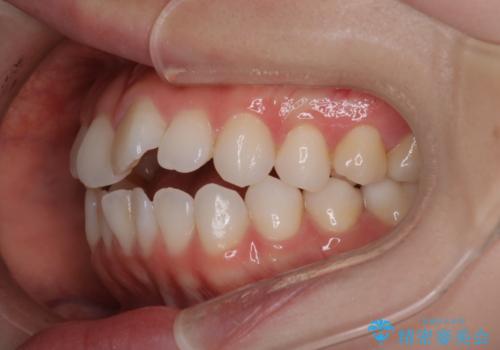

【審美装置】前歯で噛めない!抜歯しないで治したい

- 前歯の捻転とかみ合わせを主訴に来院されました。今回は抜歯をせずにIPRを実施し、並べる計画を立てました。